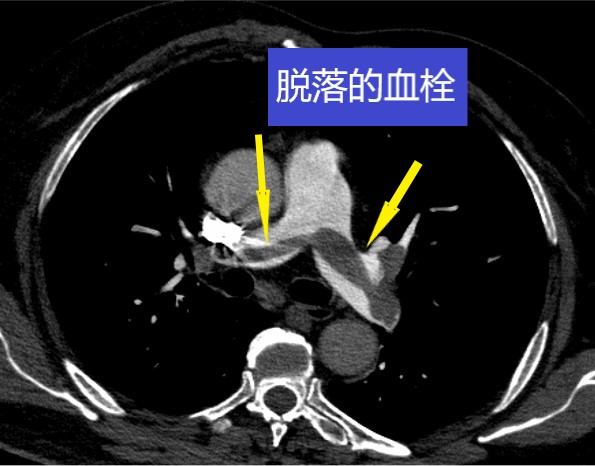

72岁的李大妈是个退休干部,平常很注意身体保养,每天都坚持步行10000步,身体一向很健康。最近一周,李大妈的左腿不明原因的肿胀起来,但是没引起李大妈的重视,继续坚持锻炼。在前两天的一个晚上,李大妈在锻炼时,一个下蹲突然感到呼吸困难,喘气费力,脸都憋紫了,话也说不出来了,家属急忙将她送到了潞河医院急诊。经过医生的急救处理并完善CTPA检查,确诊李大妈得了急性肺栓塞,随时有生命危险,李大妈被迅速收到了潞河医院急诊ICU,经过紧急救治,李大妈的喘憋明显好转了,也能正常交谈和进食了。急诊ICU的叶钢主任分析,李大妈一周前右腿肿胀,很有可能那时已经得了下肢深静脉血栓(DVT),而当她做深蹲动作时,小腿肌肉收缩挤压使血栓脱落,于是顺着血流,血栓堵塞到了肺动脉的主干,人体生存所必需的气体交换被阻断,引起严重缺氧窒息。这是一种极其凶险的疾病,若不及时处理,后果不堪设想。

尽管李大妈的病情缓解了,但是叶钢主任在检查中发现李大妈的右心室已经增大,并且心肌酶明显增高,根据急性肺动脉栓塞的危险分层,属中高危阶段,李大妈的病情仍然比较危重,遗留远期肺动脉高压的可能性很大,遂向血管外科发出了会诊申请。经过综合评估,并与患者家属进行充分沟通后,血管外科赵亮主任决定为李大妈进行肺动脉造影及肺动脉血栓抽吸溶栓手术。这是目前一项比较先进的手术技术,通过微创介入,在患者的大腿根部静脉穿刺一个小孔,将一根细导管送到肺动脉内,连接负压吸引装置,将堵塞肺动脉的大块血栓抽吸出来,而通过导管注射小剂量的溶栓药,将会把残余的小血栓溶化,从而恢复肺动脉的血流供应,满足正常的气体交换。